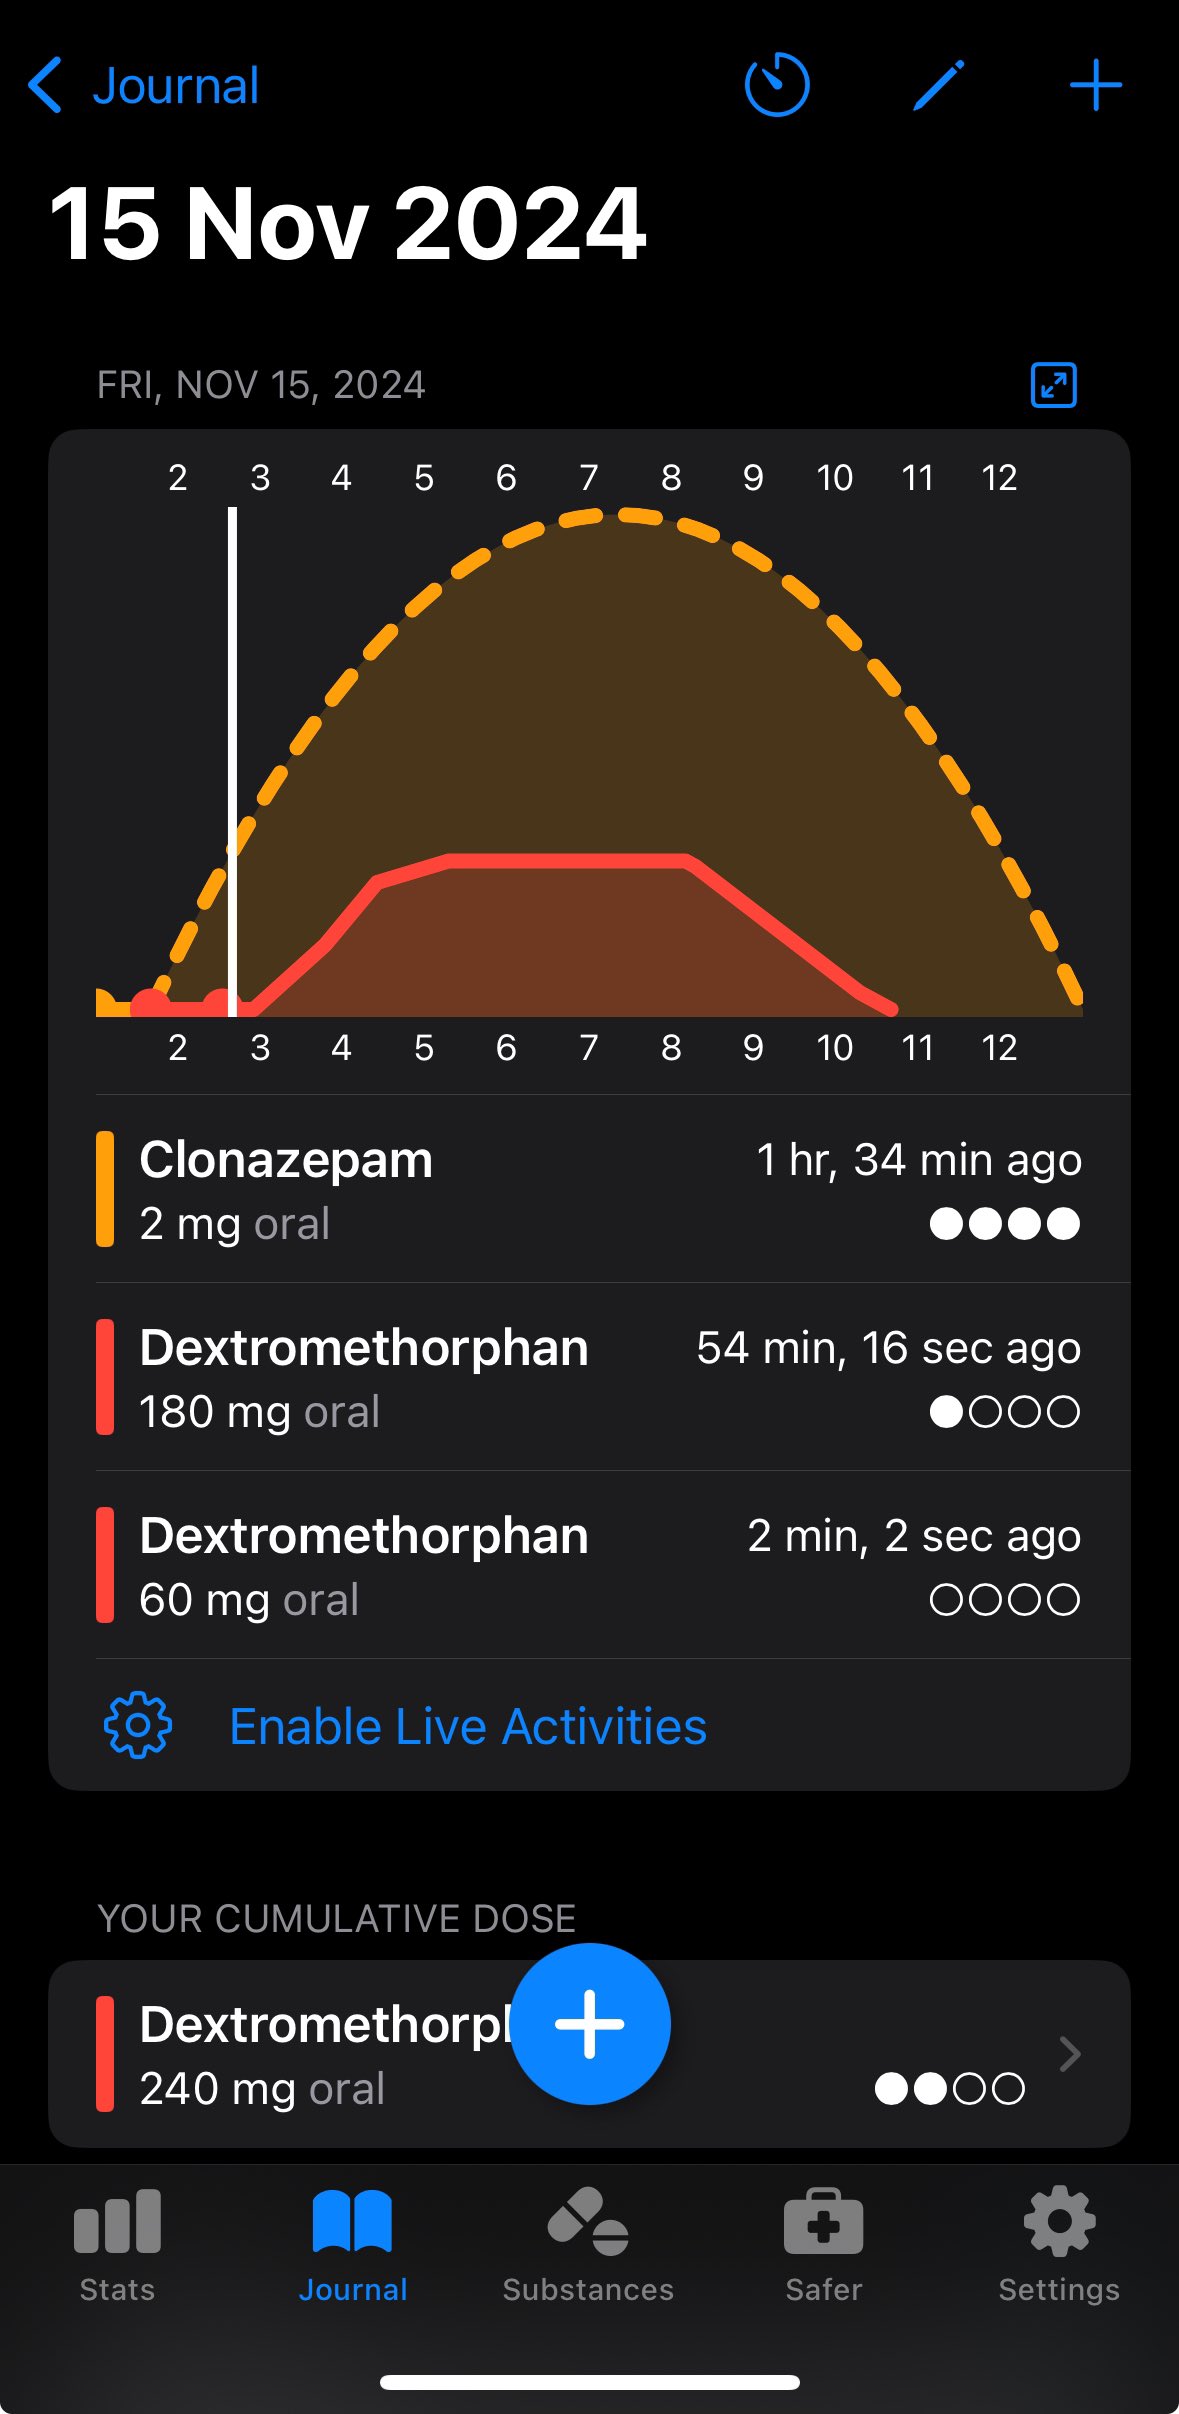

炽烈已极 @AnIncandescence@whitenightX3 journal